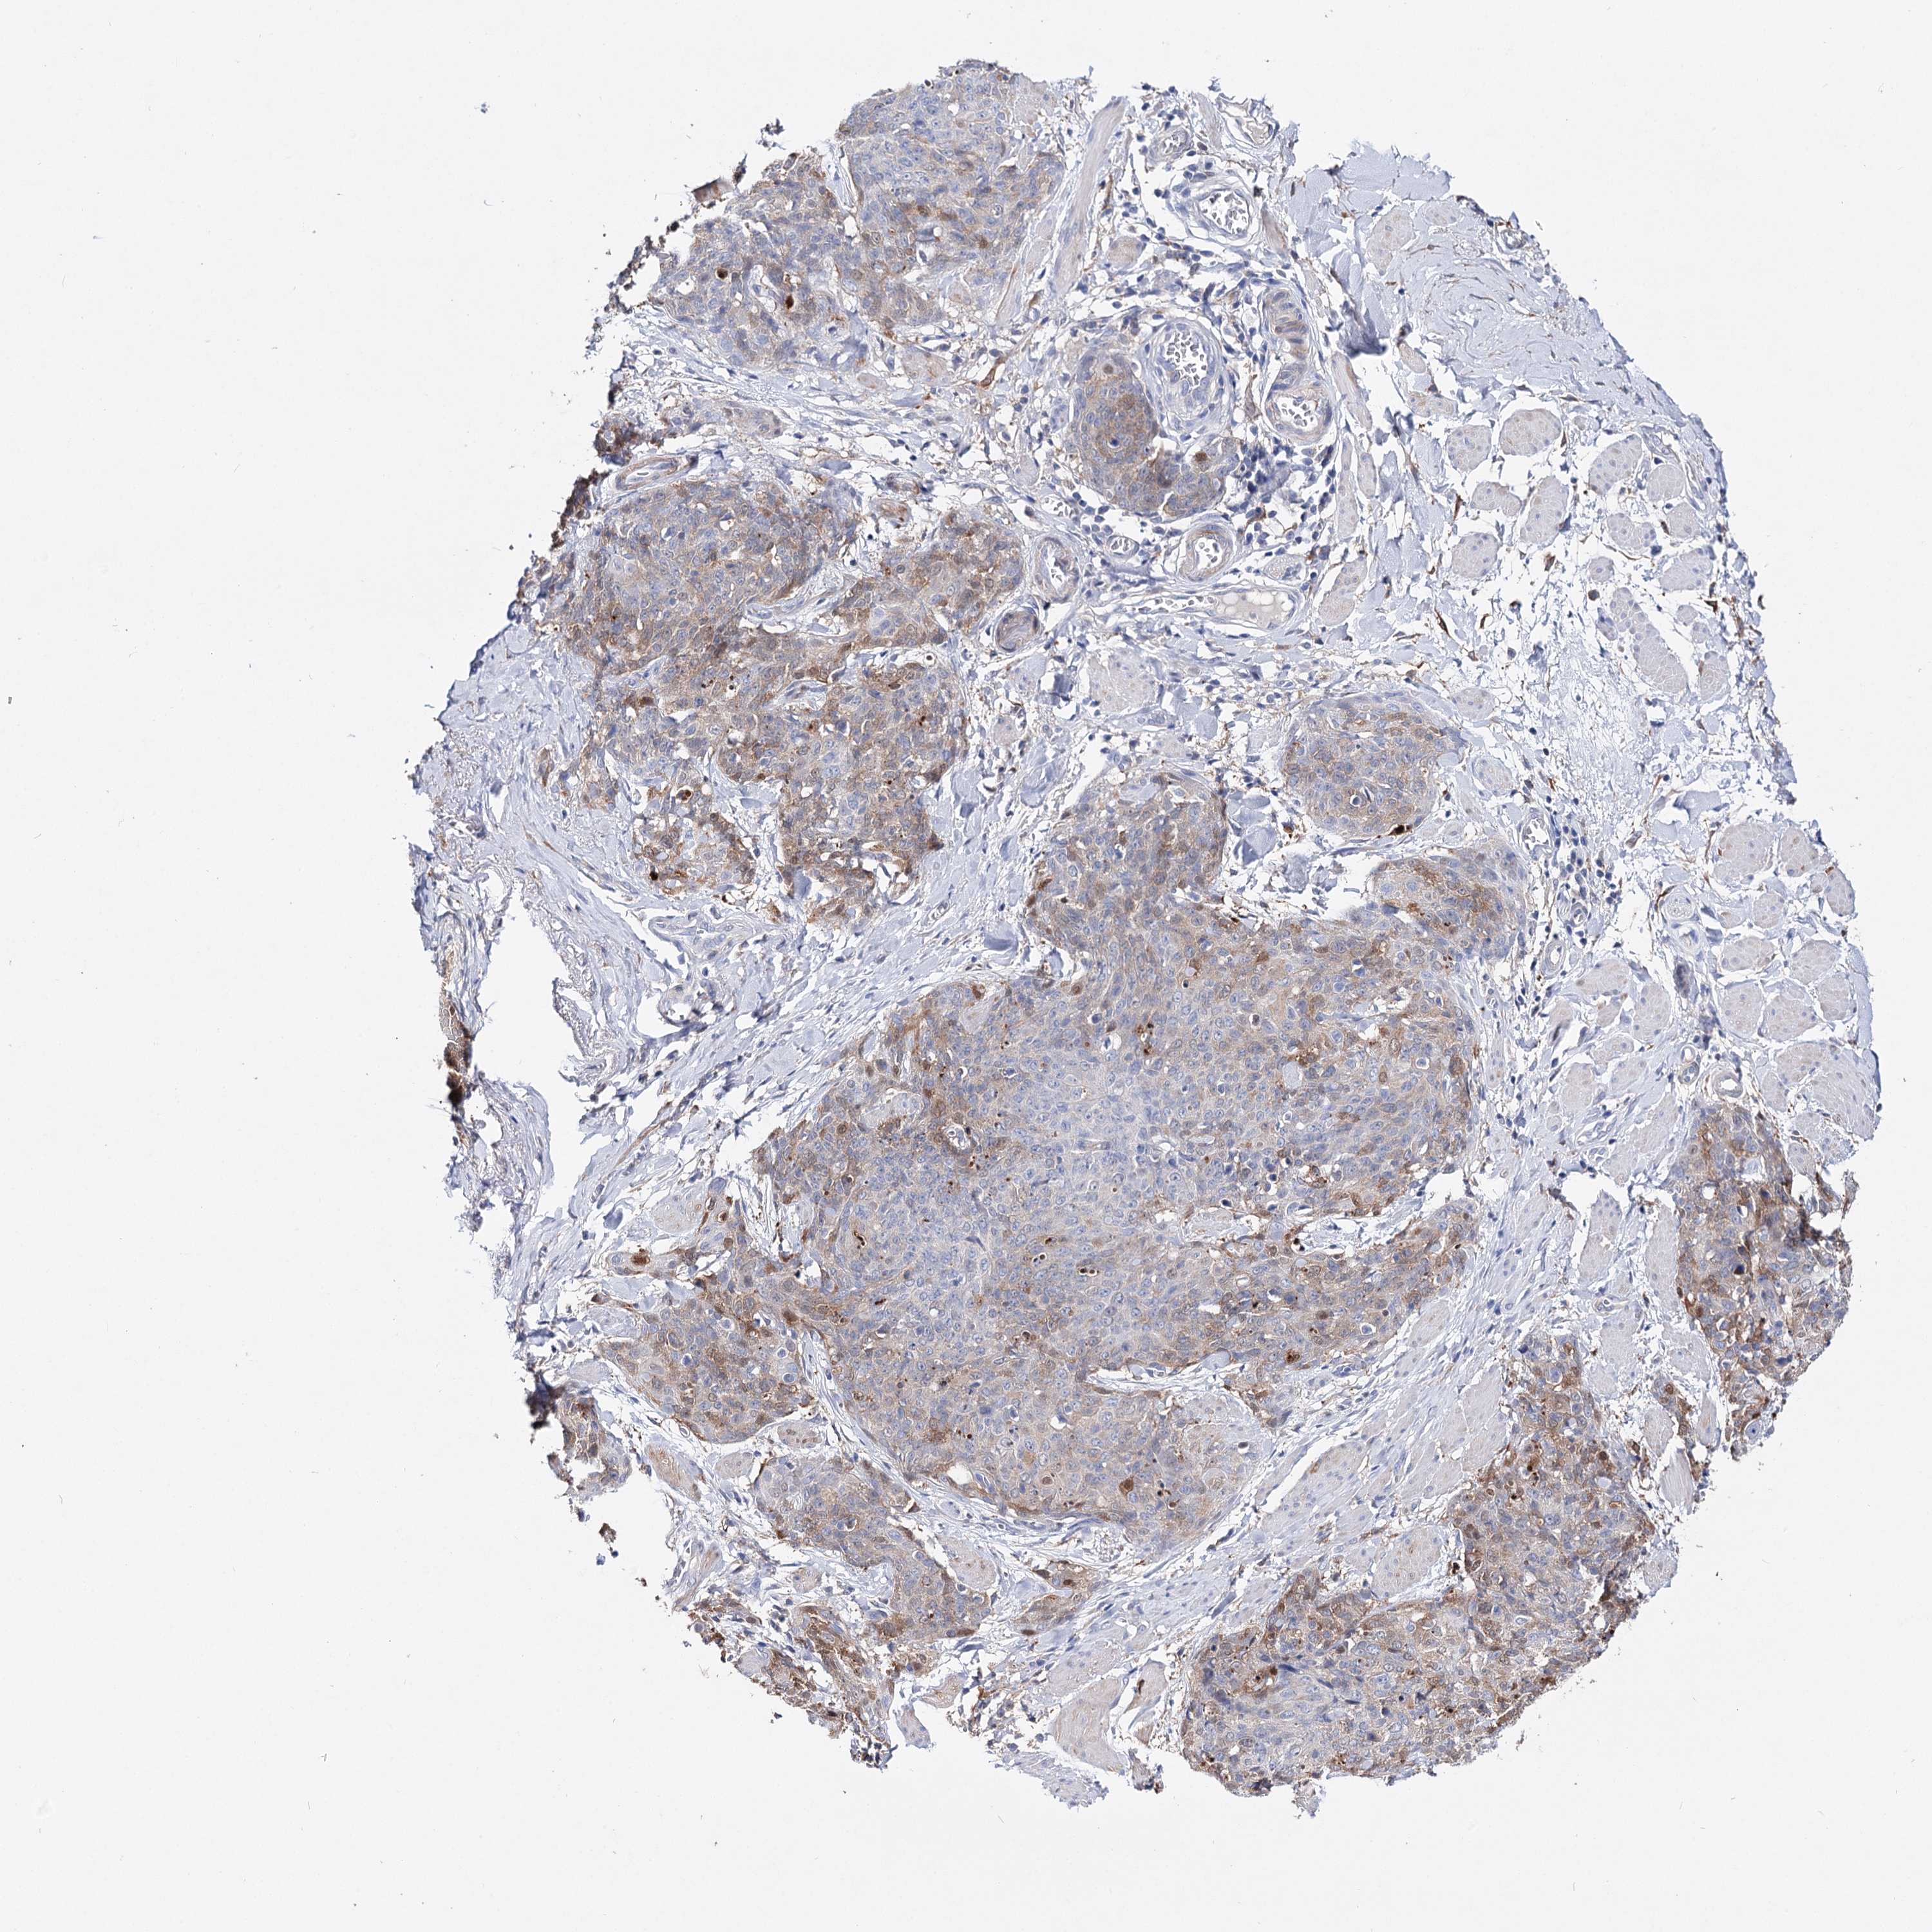

SKIN CANCER - Protein expressioni

A mouse-over function shows sample information and annotation data. Click on an image to view it in a full screen mode. Samples can be filtered based on level of antibody staining by selecting one or several of the following categories: high, medium, low and not detected. The assay and annotation is described here.

Antibody stainingi

Antibody staining in the annotated cell types in the current human tissue is reported as not detected, low, medium, or high, based on conventional immunohistochemistry profiling in selected tissues. This score is based on the combination of the staining intensity and fraction of stained cells.

Each image is clickable and will lead to virtual microscopy that enables deeper exploration of all samples and also displays staining intensity scores, fraction scores and subcellular localization as well as patient and tissue information for each sample.

Antibody HPA037786

Antibody HPA038034

Antibody HPA038867

Antibody HPA038868

Medium

Moderate

75%-25%

Cytoplasmic/membranous

Squamous cell carcinoma, NOS